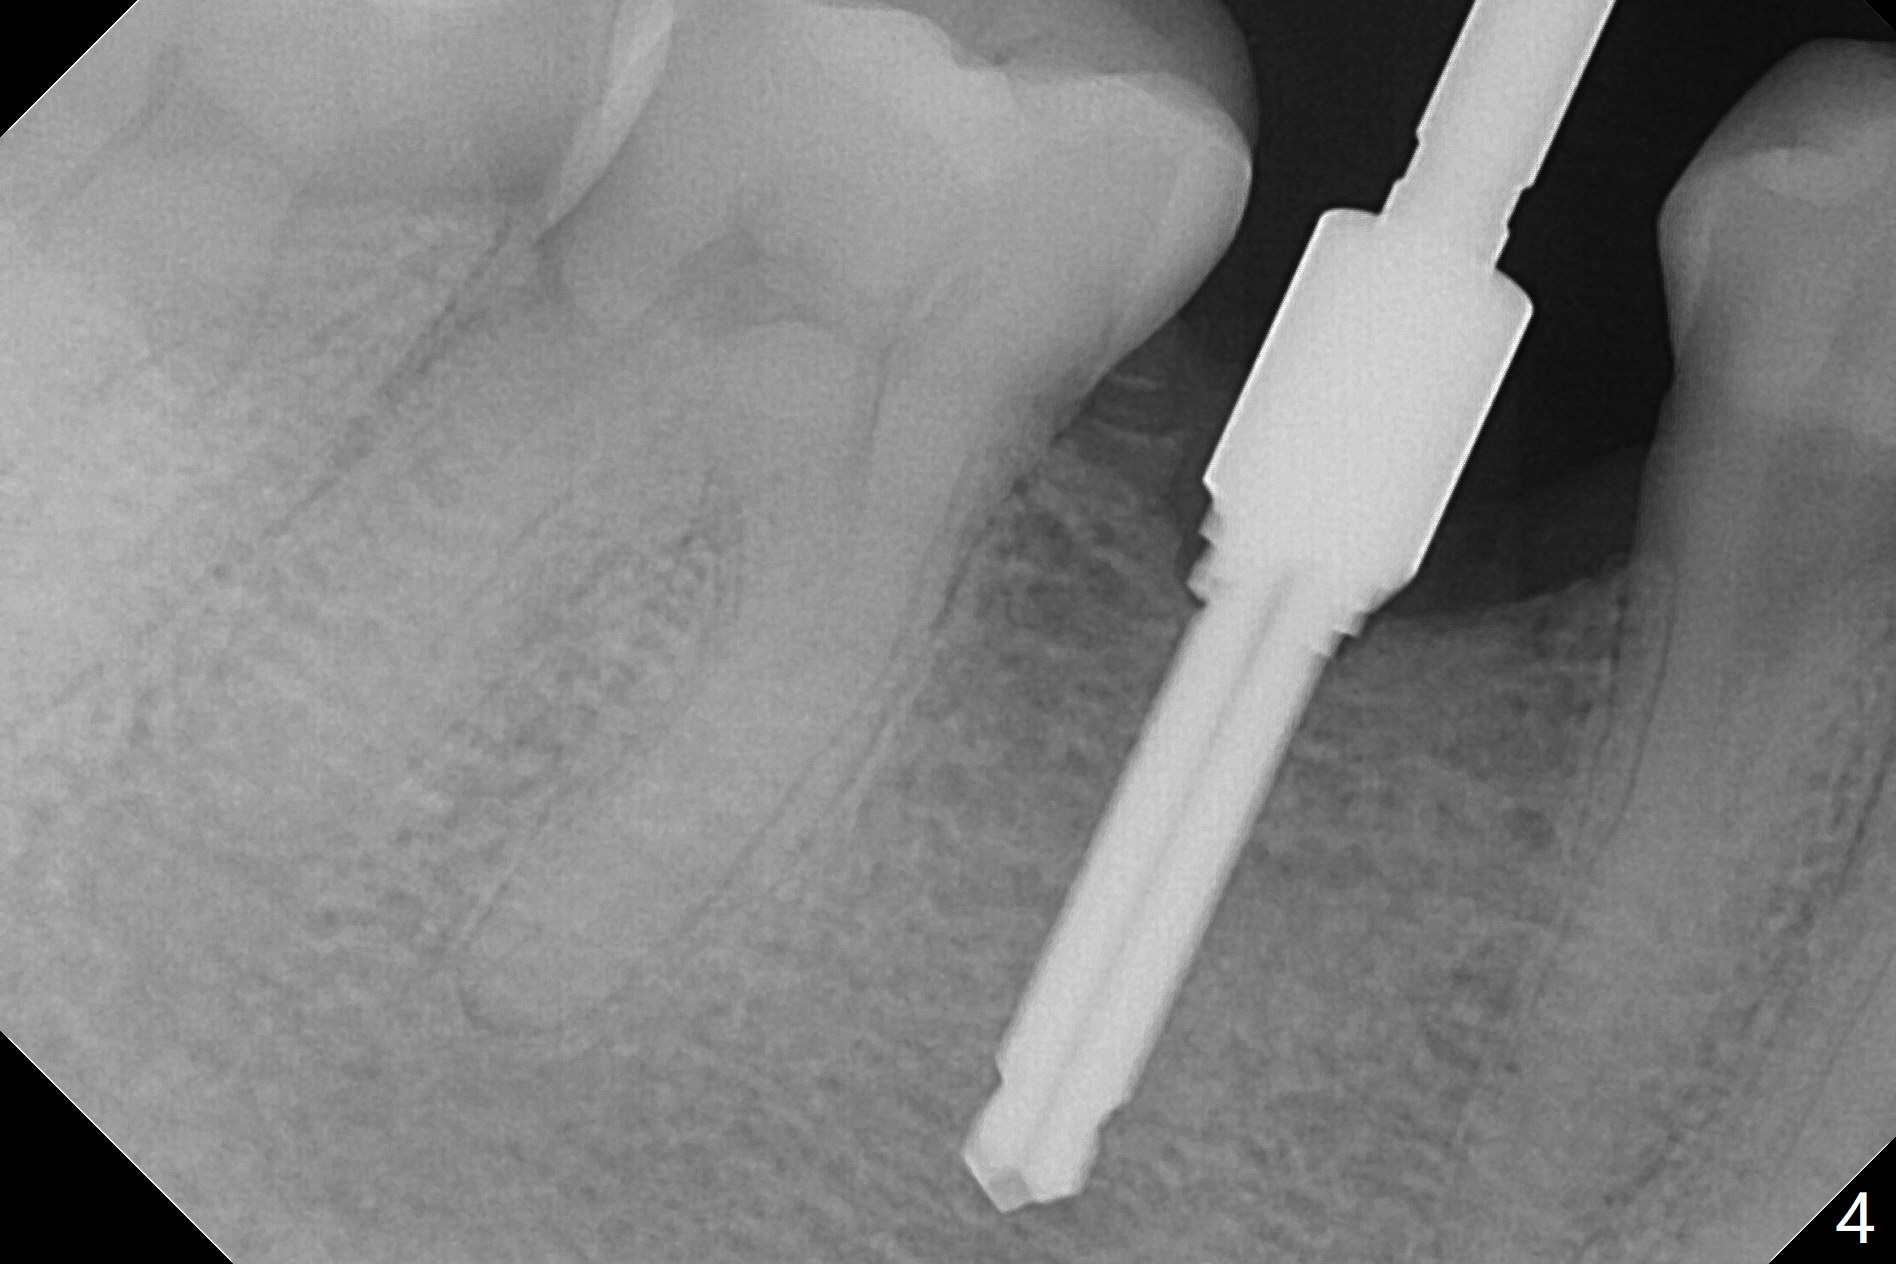

The base of the edentulous ridge at #29 looks wide (Fig.1), but the most coronal portion is the thin soft tissue (Fig.2).  It appears that there has been bone resorption since extraction.  The initial osteotomy depth is 11.5 mm (Fig.3).  Since the Mental Loop seems to be nearby, the depth of subsequent osteotomy (3 mm) remains the same (Fig.4).  Although the final depth of osteotomy is 13 mm, the implant placed is short (3.8x11.5 mm, Fig.5,6), as compared to the immediate implant (3.8x18 mm) at the contralateral side (#20).  There is mild bone resorption mesially 4 months postop (Fig.7).  The crown is loose (poor osteotomy position, guide necessity) 7 months post cementation immediately prior to 18 cementation, although there is no gross bone losss 1 year 7 months post cementation (Fig.8).